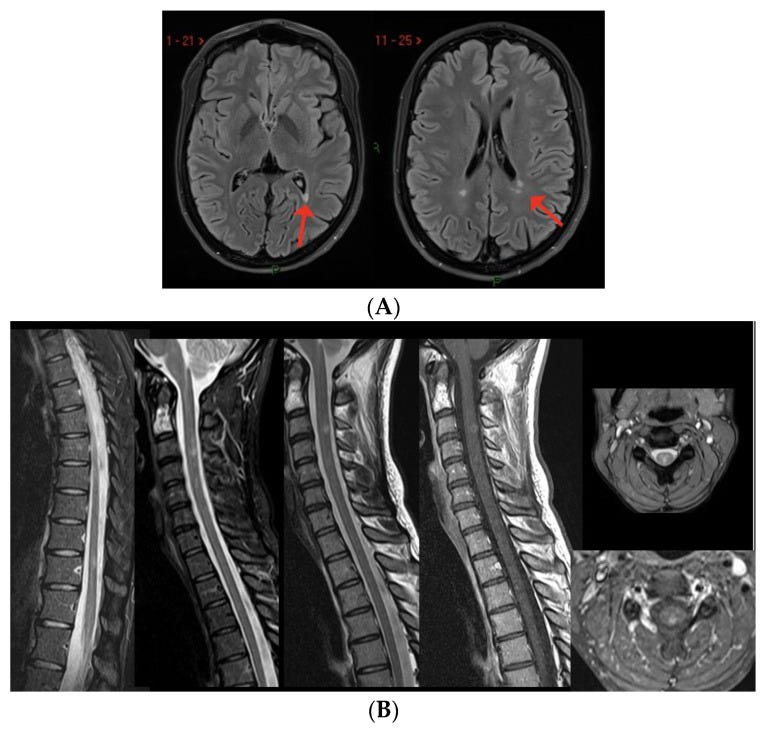

(A) Three new non-enhancing lesions in the periventricular white matter. (B) Spine MRI showing one active lesion in the cervical spinal cord and two non-enhancing dorsal lesions.